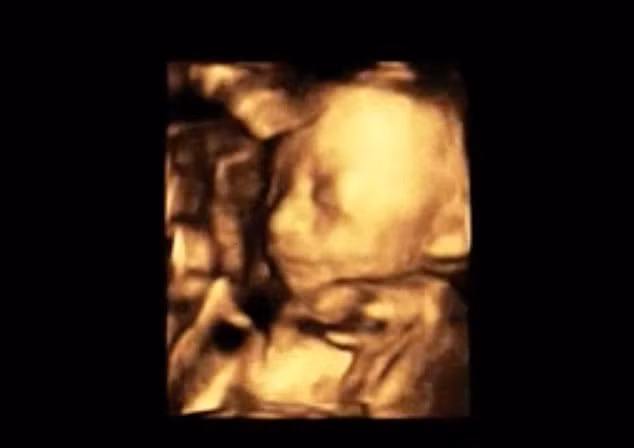

Hình ảnh siêu âm 1 tháng trước khi sinh, bé Jaycie hoàn toàn khỏe mạnh và gần như đã sẵn sàng để chào đời.